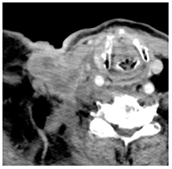

| 3 | 25–50 | 1716 | ![]() Axial CT image shows a mostly necrotic tumor in the right neck. | ![]() Axial CT image obtained 1 day after injection shows the NBTXR3 nanoparticles (arrows) in the tumor with a small amount of leakage into the surrounding soft tissues. |